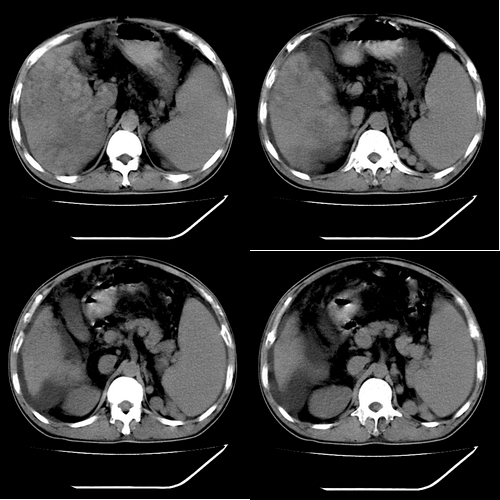

以下是引用yz在2006-6-2 12:20:00的发言:[br]肝左右叶比例失调,左叶体积明显缩小,肝边缘凹凸不平呈波浪状外观,肝左右叶可见不规则之斑片状低密度影,边界不清,以右叶为甚,肝门区增宽,增强后于动脉期病灶不均匀强化,门脉及延迟期均呈低密度,门脉主干及其右支无强化,以门脉右支明显,其内可见低密度影充填,门脉主干周围可见强化的细小侧支循环血管影。脾大,脾门血管明显增粗,脾后左侧膈脚前可见串珠状增粗强化血管影,并见胸腹水征。[br]1、考虑为弥漫性肝癌并肝门静脉主干及其右支癌栓形成,门脉海绵化。[br]2、肝硬化,脾大并门脉高压。[br]3、双侧少量胸水、腹水。